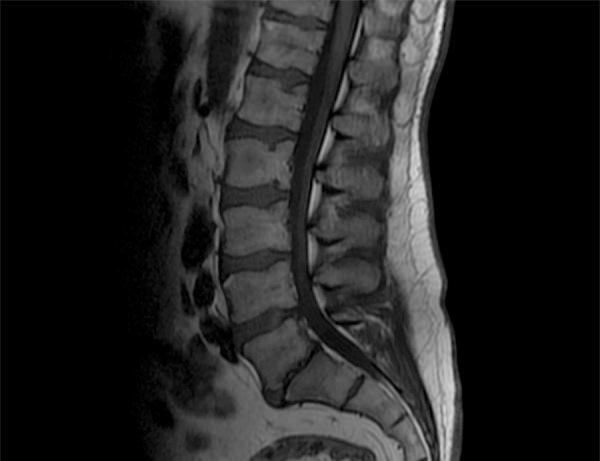

In the group of patients diagnosed with RT (refractory thrombocytopenia) and in the group diagnosed with RA (refractory anemia), 100% of lumbar spine images in T1- and T2- weighted sequences assessed together showed increased signal intensity. In patients diagnosed with RAEB (refractory anemia with excess blasts), MRI showed decreased signal intensity in 76.5% of subjects in the sequences analyzed together. In the group of patients with increased LDH (lactate dehydrogenase), 22 patients (55%) showed decreased signal intensity in the combined analysis of T1- and T2-weighted sequences. Among transfusion-dependent patients, 20 scans (60.6%) showed decreased signal intensity.

As the risk category of MDS increases towards high - bad risk, decreased signal intensity is observed in lumbar spine MRI in T1- and T2-weighted images in all studied stratification scales. There is a positive correlation between decreased signal intensity in lumbar spine MRI examinations and increased LDH level in blood serum, as well as dependence on blood product transfusions, especially packed red blood cells.